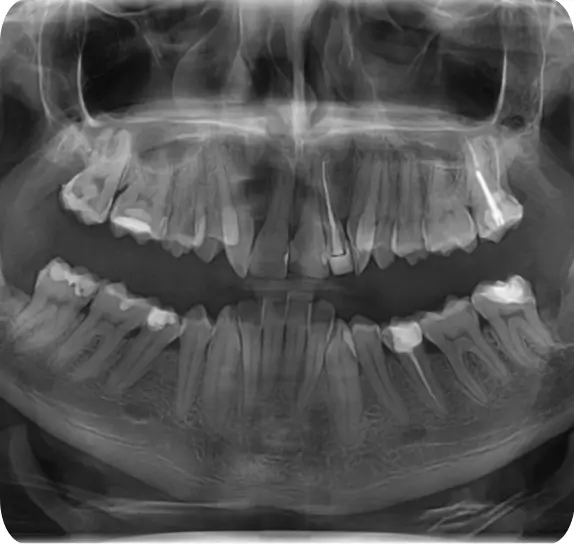

Radiografia dentară este esențială în procesul de diagnosticare și tratament al afecțiunilor dentare. La Edenta Radiologie și Imagistică Medicală, pacienții beneficiază de tehnologie de ultimă generație pentru obținerea unor imagini clare și detaliate ale structurii dentare. Aceste radiografii permit medicului stomatolog să identifice cu precizie problemele ascunse, cum ar fi cariile interdentare, infecțiile la nivelul rădăcinii sau eventuale fracturi dentare.

Un diagnostic corect este primul pas către un plan de tratament eficient și personalizat. Radiografia dentară oferă informațiile necesare pentru a dezvolta un plan de tratament care să răspundă nevoilor specifice ale fiecărui pacient. În funcție de rezultatele radiografiei, medicul stomatolog poate decide asupra pașilor următori, care pot include intervenții chirurgicale, tratamente ortodontice sau alte proceduri stomatologice.

Punem accent pe siguranța pacientului și pe acuratețea diagnosticului. Radiografiile dentare nu doar că ajută la stabilirea unui diagnostic corect, dar și la monitorizarea progresului tratamentului, asigurând astfel rezultate optime pentru sănătatea orală a pacienților noștri.

Tehnologia CBCT furnizează imagini tridimensionale precise ale maxilarelor, utilizând o doză redusă de radiatii, generând o imagine detaliată. Software-ul permite analiza în trei planuri, o componentă crucială pentru diagnostic și planificare virtuală a tratamentelor dentare, inclusiv a implanturilor, diagnosticând anomalii endodontice și parodontale, analizând ATM-ul și ghidând intervențiile chirurgicale orale.